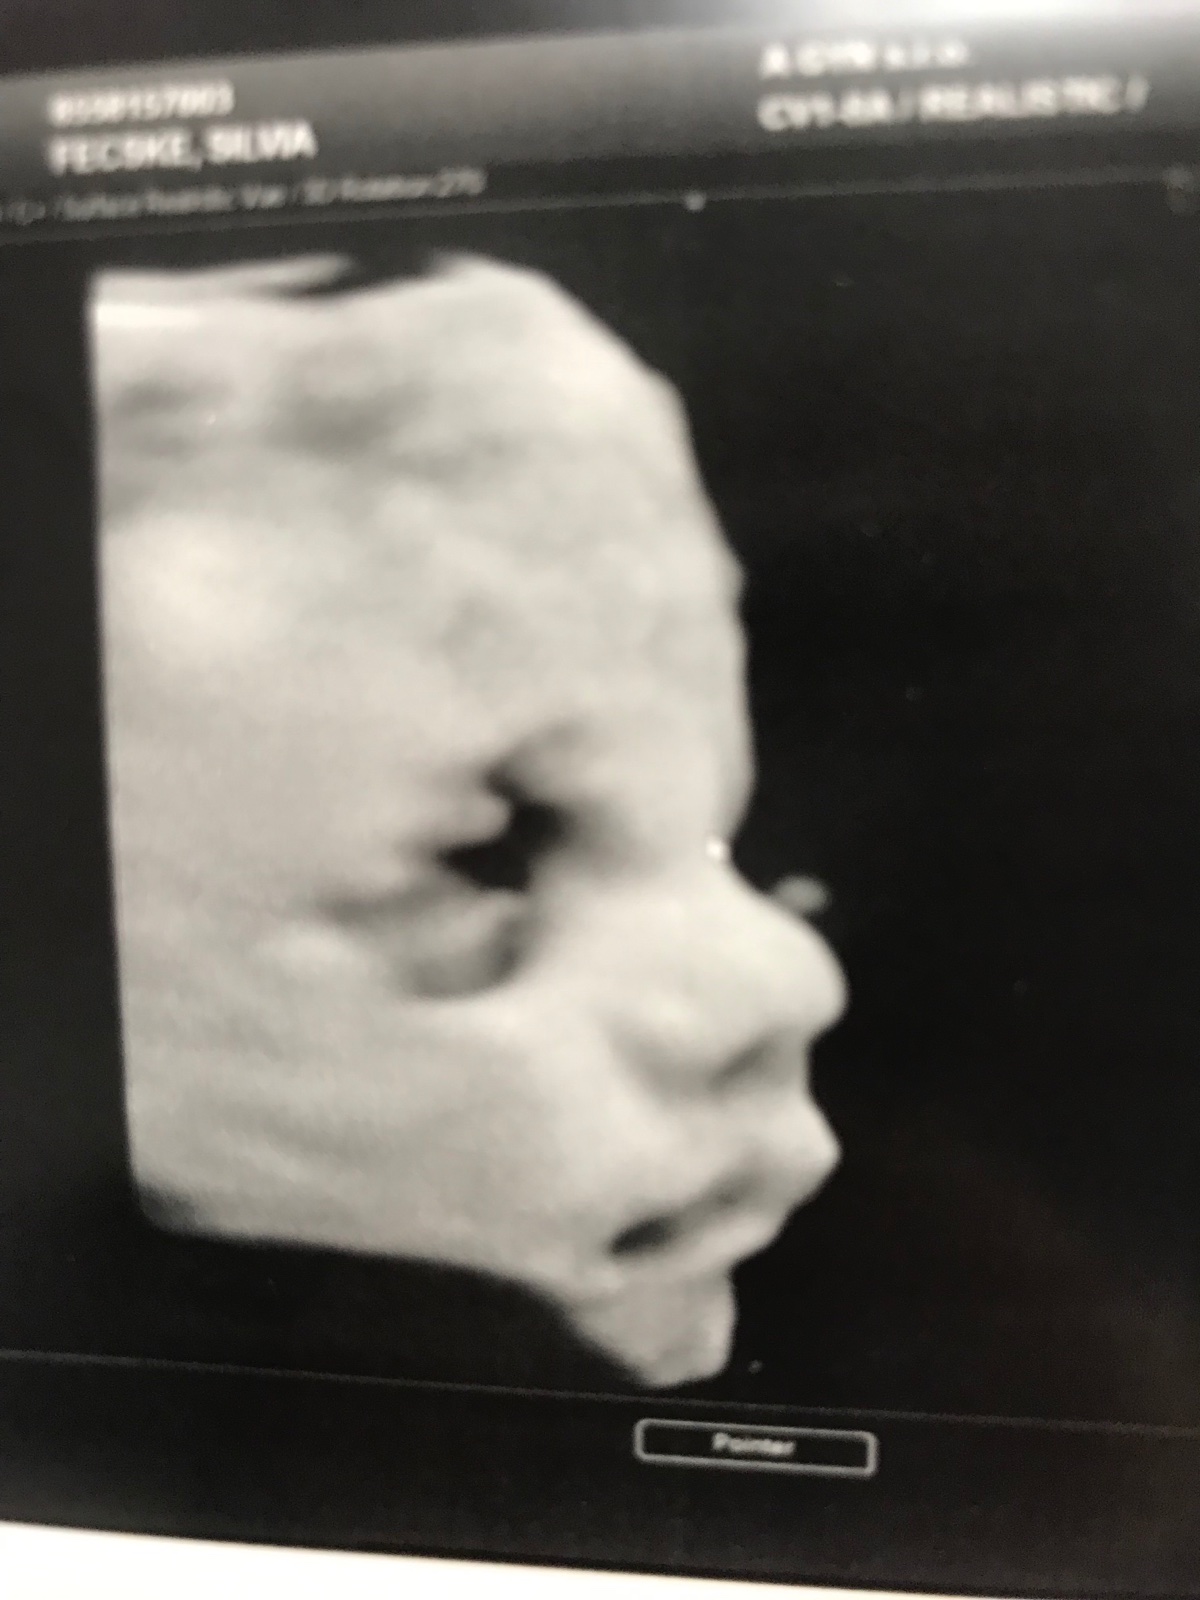

@melmel78 ahoj moja tak sa nám už isto pekne gulatis ja som ti už ako tank😆..ale už iba dva týždeň a koncim v práci už odratavam 😉😀..no tie kŕče povedz dr ..snáď je to len tým že rasties..ja sa citim úplne v pohode akurát moje heslo hlava by chcela ale telo nevládze ..tiež idem piatok do poradne a na 3-4D usg ideme prvý krát tak sa tešíme s muzom na našu princeznú ideme zo zvedavosti už tak na poslednu chvilku..a meno už máte vybraté??

@skovarik tiez dufam, ze len rastom su tie krce, clovek ma strach z kazdej bolesti, ktora nie je normalna. Zajtra mam poradnu, opytam sa na to 🙂. Dnes mi je fajn, aj tato noc bola ok, relativne bez krcov. Jaj ty uz potom ides na matersku 😘😇❤ A na 4D ku komu idete? My az 13/12 ideme na morfologiu a tiez sa objednam na 4D nech mame pamiatku na krpca 🙂

@melmel78 tak mne tiež kade tade pichá ale neako to neriešim však tam je človek čo sa tlači s mojimi orgánmi 🤪😂..predpokladam že to tak ma bit..ja idem na usg len mojej dr do ambulancie len to bude robiť dr Rukavicova z kramarov ona sa tomu venuje 60€ ma to tam bude stať...veru na materskú ani verit sa mi nechce len stále neviem kam pôjdem rodit🙈😆 neako sa neviem vymacknut lebo sto ľudí sto názorov ..tak sa drzkaj a pohladkaj babo a ozaj to meno už máš?